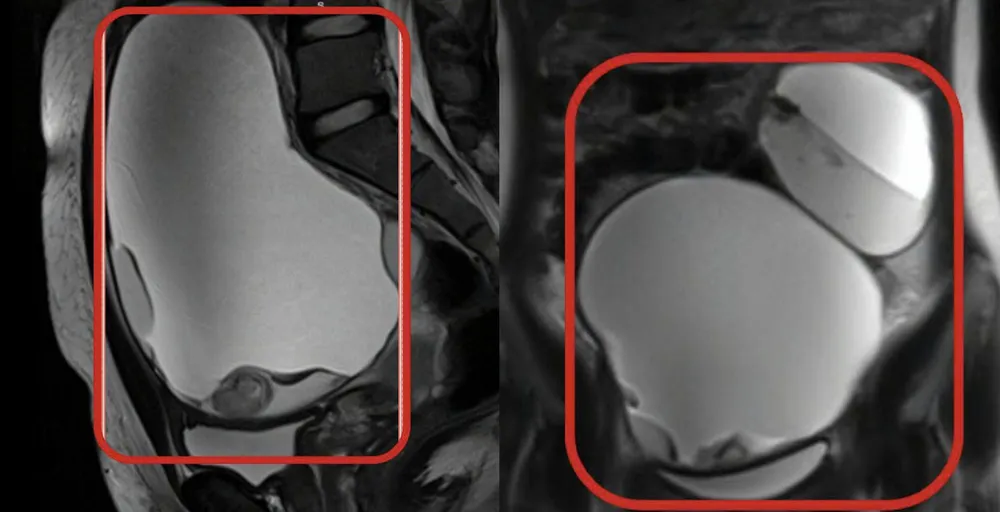

Kết quả MRI cho thấy tử cung không bất thường nhưng hai buồng trứng có 2 khối u bì bị xoắn - một biến chứng cấp cứu nguy hiểm. Khối u buồng trứng phải có kích thước khoảng 13×15 cm, khối bên trái 8×10 cm.

Hai khối u bì buồng trứng kích thước lớn chứa tóc, da, răng